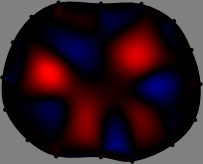

Figs. 3 and 4 compare the performance of the proposed FER method in (20) with the standard regularized least-squares method ((19) when is the identity matrix). The regularization parameter of the standard method was heuristically chosen for its best performance, and the parameter of the FER method was set to be one of three different values . The injection current was 1 mA at 100 kHz, and the frame rate was 9 frames per second. The reference frame at was obtained from the maximum expiration state. The measured data, , represent the voltage differences between each time and . The blue regions, which denote where conductivity decreased by inhaled air, increased during inspiration and decreased during expiration. The FER method with was clearly more robust than the standard method that produced more artifacts originated from the inversion process.

| Standard | |

||||||||||

| FER () | |

| FER () | |||||||||||